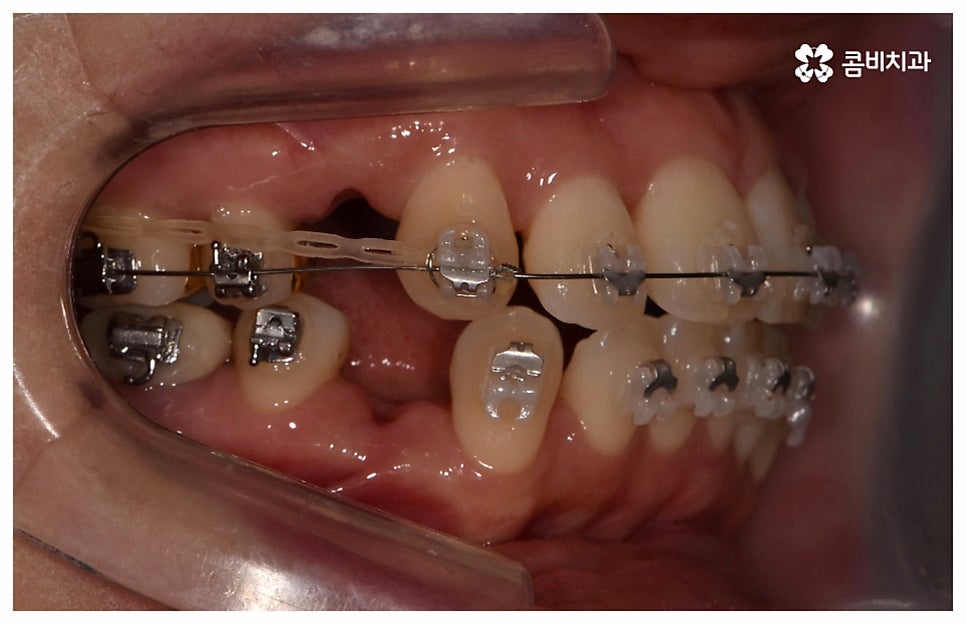

검진 후 부분 교정이 가능하지 않은 케이스라고 해도 요즘은 심미적인 교정 장치가 많이 나와 있으며 장치 자체로 인해 결과에 미치는 영향이 크지 않기 때문에 자신의 상황에 맞는 장치를 직접 선택할 수 있으니 의료진과 충분히 상담을 해 보시면 도움 받아 보실 수 있을 거예요. 특히 치아 색상의 브라켓을 이용한 세라믹 장치들이 심미성이 뛰어난데, 그 중에서도 자가결찰방식을 이용한 클리피씨 교정 장치를 이용하면 눈에 크게 띄지 않을 뿐 아니라 보다 적은 힘으로 부드럽고 지속적인 치아 이동을 가능하게 하기 때문에 통증도 줄이고 전체 교정 기간 역시 단축시킬 수 있다는 장점이 있으니 이에 대해서도 자세하게 알아보시길 바라고 있습니다.

교정의 경우 보통 1년 반에서 2년 정도로 짧지 않은 기간이 걸리기 때문에 장치가 겉으로 드러나는 것에 대해 부담을 느끼시는 중장년분들이 많이 있습니다. 하지만 환자분들의 상황에 따라 부정 교합 정도가 심각하지 않고 골격적인 원인이 크지 않다면 6~8개월 정도 소요되는 부분 교정으로 필요한 부위만 보다 빠르고 간편하게 바로잡을 수 있으니 먼저 검진부터 진행해 보시길 권유드리고 있어요.